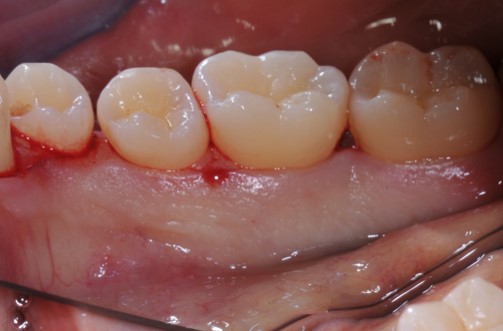

02/22 - Pre-surgical clinical situation, lingual view.

Deep intrabony defects treated using Straumann® Emdogain® - Dr. M. Stefanini